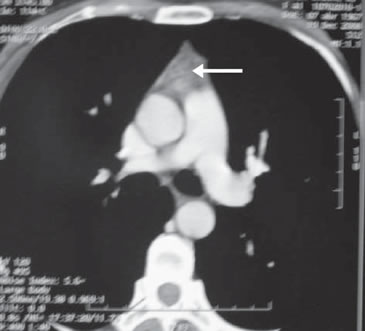

Se inició tratamiento con L-tiroxina (Eutirox®) en dosis ascendentes hasta llegar a 150 mcg/d (TSH: 0,06 uUI/mL). Al completar un año de operada, la ecografía cervical fue totalmente negativa, pero la Tg estimulada fue 8,7 ng/mL (TSH: 64 uUI/mL) con negatividad de los Ac anti Tg. Después de una segunda dosis de 100 mCi de I131, el rastreo sistémico sólo mostró un leve aumento en la captación de I131 en línea media baja, en situación retro esternal (Figura 2). El hallazgo descrito correspondía a captación mediastínica. En el control a los 18 meses, la Tg (sin estímulo) era indetectable (< 0,5 ng/mL), persistiendo la negatividad de los Ac anti Tg. Al completar el segundo año de seguimiento, la ecografía cervical no mostró ningún hallazgo patológico. Dado el antecedente de captación cervical baja, se solicitó un TAC cervical y torácico que mostró un lecho tiroideo libre y ausencia de adenopatías; en el mediastino superior, se describe una imagen triangular en el espacio prevascular, que se interpretó como persistencia del timo (Figura 3).

Figura 2. Exploración sistémica post segunda dosis de I131 (100 mCi), con captación intratorácica. La fl echa señala la imagen del timo.

Figura 3. Tomografía computada de tórax mostrando la presencia de timo.

Este caso ejemplifica como, en situaciones como la descrita, se está proclive a interpretar la captación cervical anterior baja del isótopo como parte de la enfermedad tumoral, más aún si el genio biológico del tumor es agresivo, como sucedió en nuestra paciente, y asociado a Tg positiva (8 ng/mL). Sin embargo, en el control efectuado a los dos años de la cirugía, y habiendo recibido dos dosis de yodo radioactivo, la ausencia de hallazgos ecográficos, y la negatividad de la tiroglobulina, pero con persistencia de la captación mediastínica alta de I131, hizo plantear una causa espuria de esa captación, siendo la primera de ellas la persistencia del timo. Las imágenes del TAC confirman esa hipótesis diagnóstica (Figura 3).